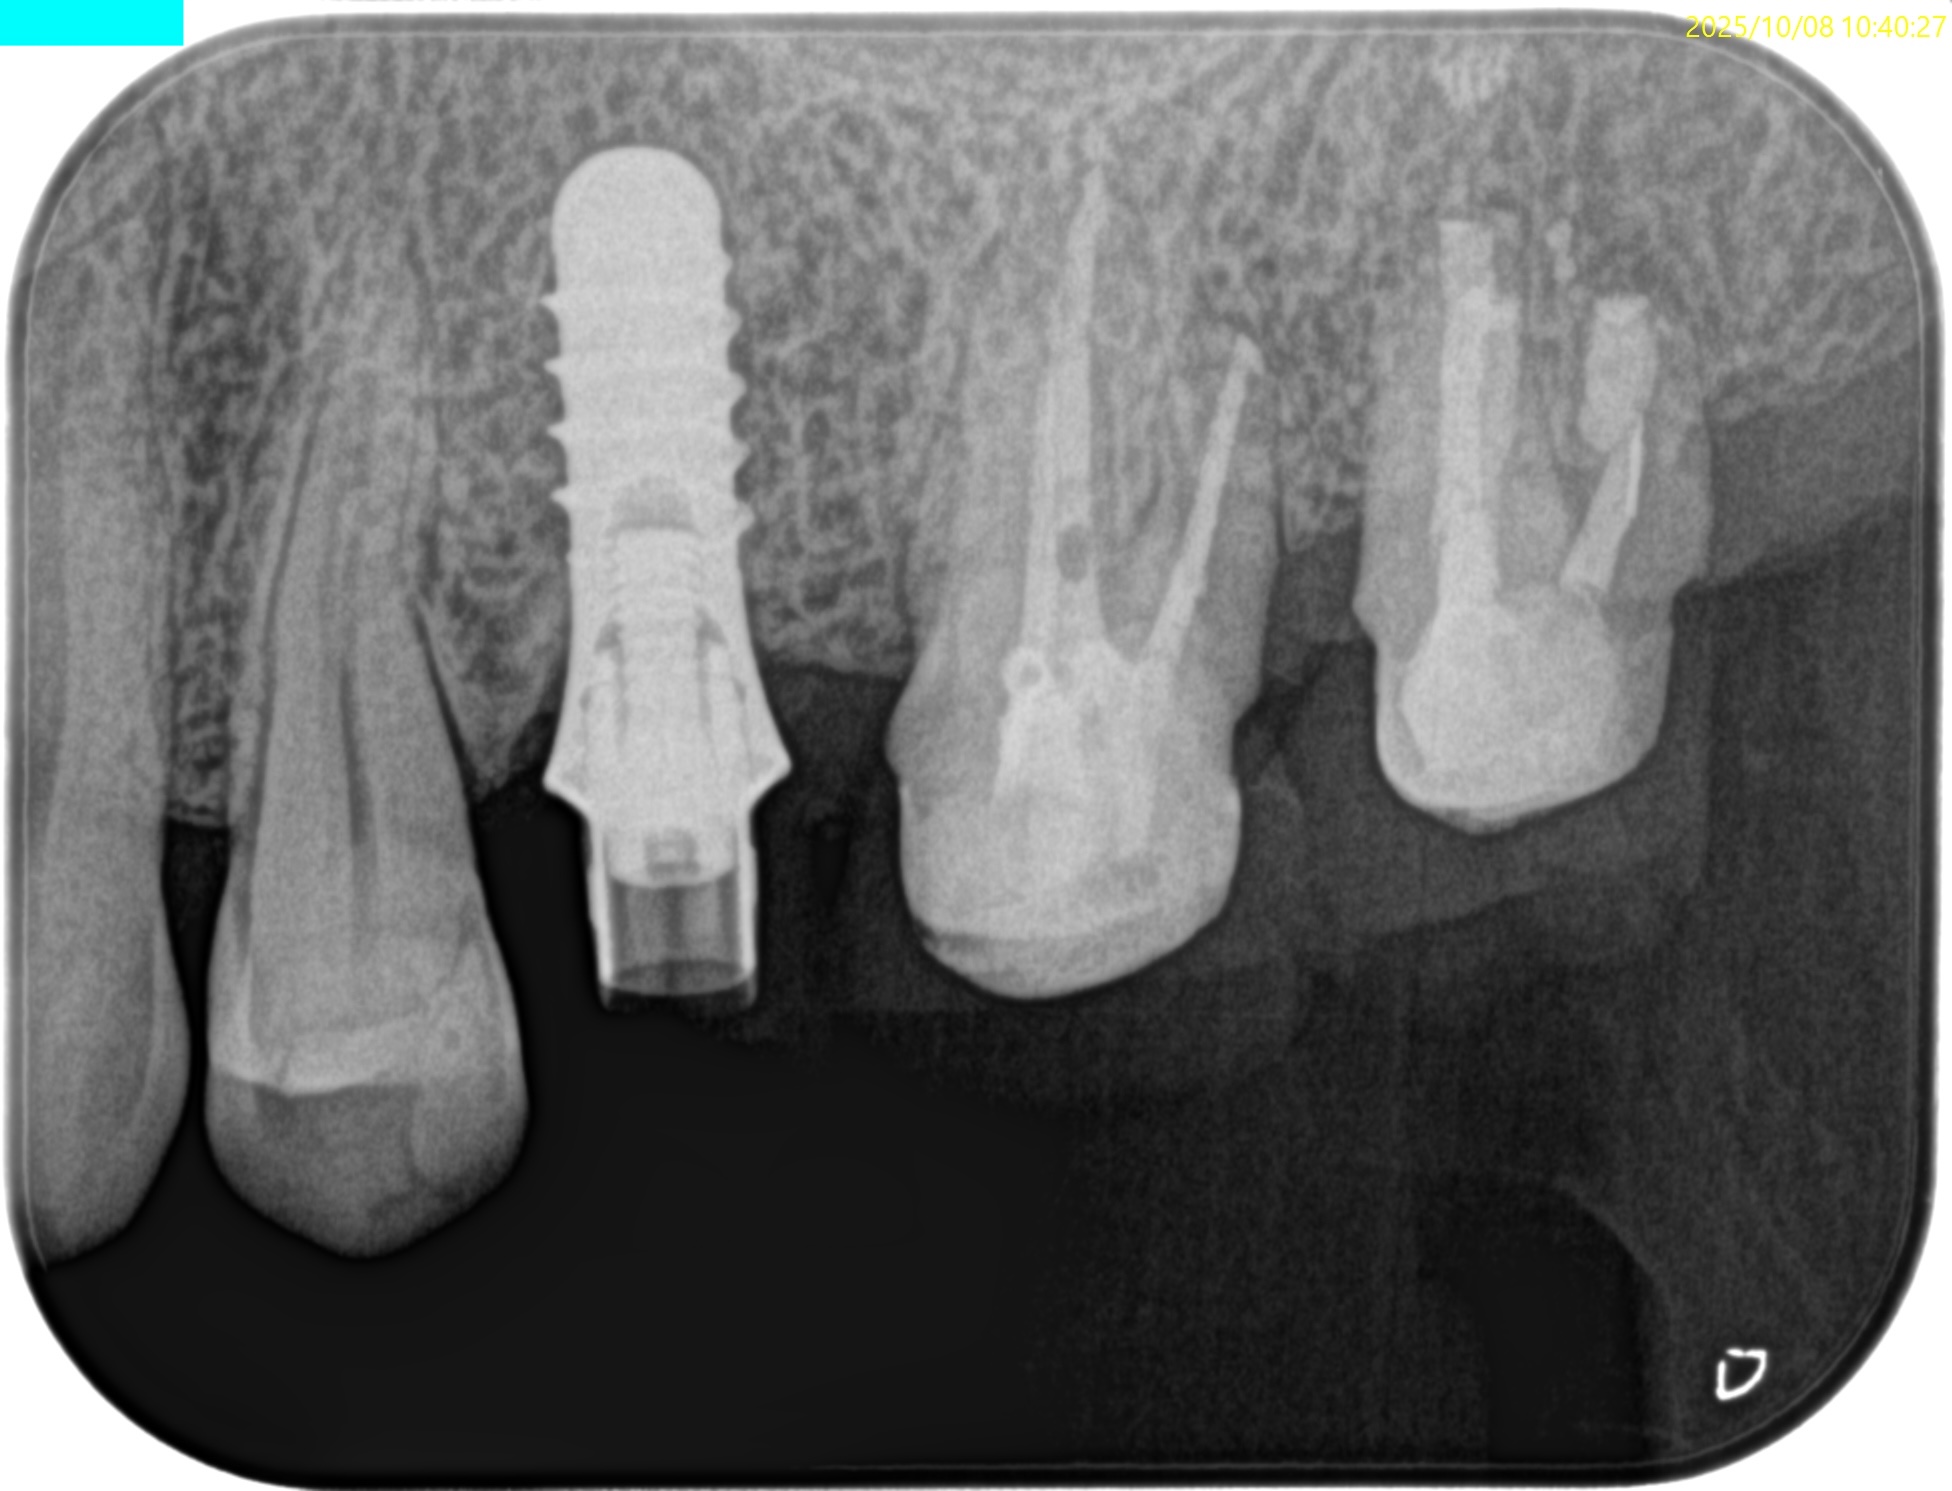

#15 Intentional Replantation 6M recall(2025.10.8)

#15 MB

#15 DB

#15 P

治療直後と比較した。

歯槽骨の改善が大幅にみられた。